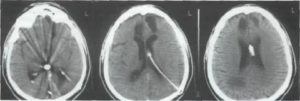

- КТ черепа и головного мозга для исключения гидроцефалии, новообразований основания черепа, выявления менингоцеле.